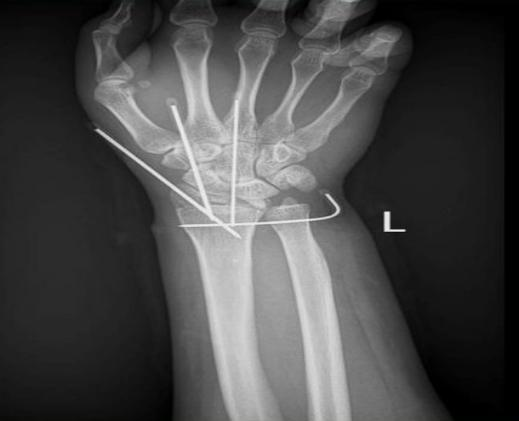

近期,易先生在石料矿工作时不慎被机器致伤左手腕部,导致尺桡骨远端骨折及腕关节脱位、腕部血管肌腱神经损伤,伤后被紧急送至我院手足显微外科就诊。

手术历经4小时顺利完成 我院手足显微外科王建锋团队接诊后立即迅速启动绿色通道,在检验科、放射科、超声医学科、手术麻醉科的紧密协作与配合下,不到1小时便为患者急诊行腕部清创+断腕再植术。手术历时4个多小时,成功保住了患者的肢体。术后,护理团队为其制定个性化康复计划,帮助易先生逐步恢复手腕活动功能。